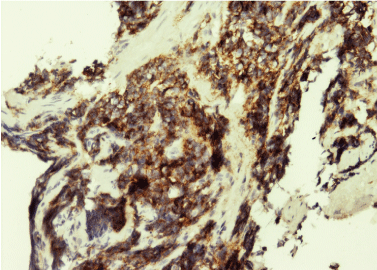

A 63-year-old female presented to urology outpatient department with complaints of hematuria. The patient's urine examination was positive for blood with microscopic presence of 3‑7 RBC/hpf. The ultrasonography of the urinary bladder revealed a large flat mass measuring 4 × 2 cm arising from dome and anterior wall of urinary bladder. Contrast enhanced computed tomography scan confirmed the anatomical location of the mass. Patient underwent cystoscopy and transurethral resection (TUR) of the mass. Microscopic sections showed sheets and nests of loosely cohesive, small round to oval cells with hyperchromatic coarsely granular nuclear chromatin, scant cytoplasm and marked crushing artefact (Figure 1). Immunohistochemically, the tumor cells stained positive for cluster of differentiation (CD) 56, chromogranin A, and synaptophysin, (Figure 2A, Figure 2B and Figure 2C) and were negative for NSE, epithelial membrane antigen and leucocyte common antigen. The pathology of resected mass was primary small cell carcinoma invading muscularis propria. The patient's whole-body scan had no evidence of metastasis. Faced with the diagnosis, the attending team chose to perform radical cystectomy (RC) and ileal conduit urinary diversion and standard lymph node dissection under general anesthesia. The patient had no complications after RC and she was discharged on day 19 after RC. She was also given neo adjuvant chemotherapy (received four cycles of cisplatin, gemcitabine and paclitaxel) and is doing well.

Figure 2A: Synaptophysin positivity in tumor cells (100X). View Figure 2A

Figure 2B: Chromogranin positivity in tumor cells (100X). View Figure 2B

Figure 2C: CD56 positivity in tumor cells (100X). View Figure 2C